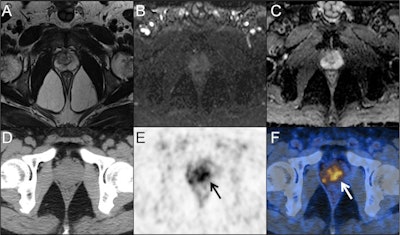

A 55-year-old man presented with a persistently elevated prostate-specific antigen (PSA) range of 4.37-6.82 ng/ml over a period of one year. Magnetic resonance imaging (MRI) (A, T2-weight imaging; B, DWI imaging; C, ADC map) didn't reveal the presence of any malignant lesions. PET/CT images (D, CT; E, PET; F, fusion) showed intensive prostate-specific membrane antigen (PSMA) uptake in the center gland and right periphery of the prostate (arrows). According to the predictive model, the probability of clinically significant prostate cancer for this lesion is 0.67 (> 0.35). Subsequent prostate biopsy result in a Gleason score 4 + 3 prostate cancer. Image courtesy of Cancer Imaging through CC BY 4.0.In the analysis, they compared a number of diagnostic indicators between the groups. They found a prediction model comprised of Ga-68 PSMA PET/CT maximum standardized uptake value (SUVmax), prostate volume (PV), and free PSA/total PSA (a ratio indicating risk) performed best for identifying clinically significant cases.